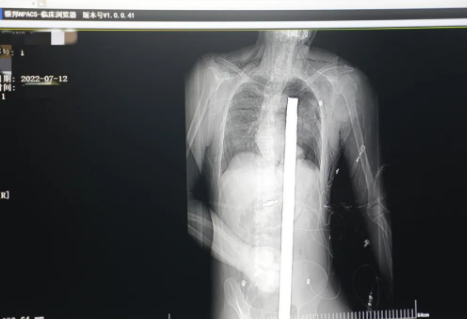

突發(fā)!太疼了,1.2米長(zhǎng)的螺紋鋼從男子會(huì)陰部垂直穿入胸腔......7月12日下午16時(shí)10分,西安一處工地的一名26歲工友,不慎從10多米的高空墜落,不幸的是工地上一根直徑3厘米的螺紋鋼從男子會(huì)陰部垂直穿入體內(nèi),工地上的工友們小心翼翼地將連著的鋼筋截?cái)?。情況危急,立即送往西安國(guó)際醫(yī)學(xué)中心醫(yī)院急救中心,此時(shí)正是下午17時(shí)00分。

時(shí)間就是生命!此時(shí),西安國(guó)際醫(yī)學(xué)中心醫(yī)院展開了一場(chǎng)與生命賽跑的搶救,第一時(shí)間開辟綠色通道,急診X光片及CT顯示:異物經(jīng)會(huì)陰部貫穿盆腔、腹腔到達(dá)左側(cè)胸腔主動(dòng)脈弓水平。醫(yī)院創(chuàng)傷中心立即啟動(dòng)應(yīng)急預(yù)案,劉延彤副院長(zhǎng)親臨指揮,下午17點(diǎn)48分,當(dāng)患者被送達(dá)手術(shù)室,胸外、心外、肝膽外科、胃腸外科,泌尿外科及麻醉科等多學(xué)科專家聯(lián)手對(duì)這名工友進(jìn)行“縱劈胸骨 前外側(cè)開胸探查 氣管及主支氣管修補(bǔ) 肺修補(bǔ) 血胸清除 開腹探查止血 腹膜后及盆腔探查......”手術(shù)。

情況緊急!術(shù)中探查后發(fā)現(xiàn),長(zhǎng)120cm直徑3cm的螺紋鋼經(jīng)患者右側(cè)會(huì)陰部穿入,傷及直腸,途徑膀胱后方,左側(cè)髂總動(dòng)靜脈之間傷及左腎后,經(jīng)胰腺后方在肝脾之間穿破膈肌,在下肺靜脈前方穿入左肺穿破氣管及左右主支氣管膜部,止于主動(dòng)脈弓下水平,穿入體內(nèi)的部分達(dá)到75cm。